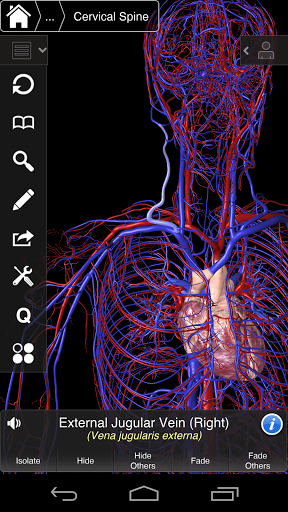

Essential Anatomy 3 représente la toute dernière technologie 3D révolutionnaire et un design innovant. Un moteur graphique 3D de pointe, construit sur mesure par 3D4Medical à partir de zéro, alimente un modèle anatomique très détaillé et fournit des graphiques de qualité exceptionnelle qu'aucun autre concurrent ne peut atteindre.

L'application représente une approche unique à l'apprentissage de l'anatomie générale. Les graphismes sont inégalés et rendent l'apprentissage, grâce à l'utilisation de contenu informatif et de fonctionnalités innovantes, une expérience riche et engageante.

⁃Veines

⁃Artères

Essential Anatomy 3 est réactif, visuellement magnifique et sans effort. L'application est entièrement 3D, ce qui signifie que vous pouvez voir n'importe quelle structure anatomique dans l'isolement, ainsi que de n'importe quel angle.

---- Plus de 4000 structures anatomiques très détaillées

---- Nomenclature latine pour chaque structure anatomique